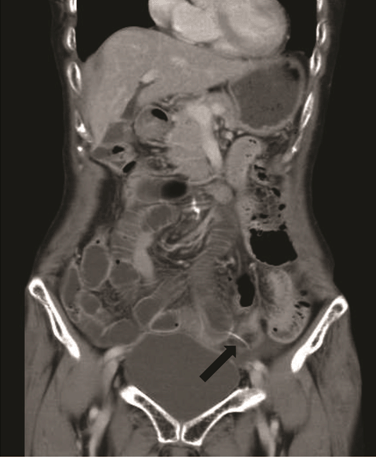

A 73-year-old female was presented to emergency department with a one-day history of increasing lower abdominal pain. The patient had attended a wedding party of her grandson and ate baked red snapper. Her past medical history was unremarkable and she was taking medication for hypertension. Her vital signs included blood pressure 119/66 mmHg, pulse rate 80 beats/min, and body temperature 36.2°C. On examination, the patient had a slightly distended abdomen with significant right iliac fossa guarding and tenderness. Her white cell count and C-reactive protein levels were 11900/mm3 and 1.24 mg/dL, respectively, indicating systemic inflammation. Abdominal computed tomography demonstrated pneumoperitoneum and fluid within the abdominal cavity, as well as dilated intestine, suggesting diffuse peritonitis due to alimentary tract perforation (Figure 1) (Figure 2). Under general anesthesia, the patient underwent diagnostic/therapeutic laparoscopy, which showed acutely inflamed ileum and purulent ascites. A foreign body, assumed to be a fish bone, was observed piercing through the small bowel wall at the ileum. As the site of perforation was not clearly determined via laparoscope, a lower median laparotomy was performed. Lavage of the abdominal cavity enabled us to detect a 2-mm ileal perforation by foreign body by confirming bubble from the perforation. Diffuse purulent peritonitis was evident in an area with adhesions. The foreign body was removed, primary suture of the intestinal perforation was performed, and the abdominal cavity was drained. Intravenous antibiotics were administered. The patient was discharged on day-5 after admission without complications.

Figure 1: Plain abdominal computed tomography showing thickened intestinal segment, localized pneumoperitoneum. Linear density crossing the intestinal wall was noted (black arrow).